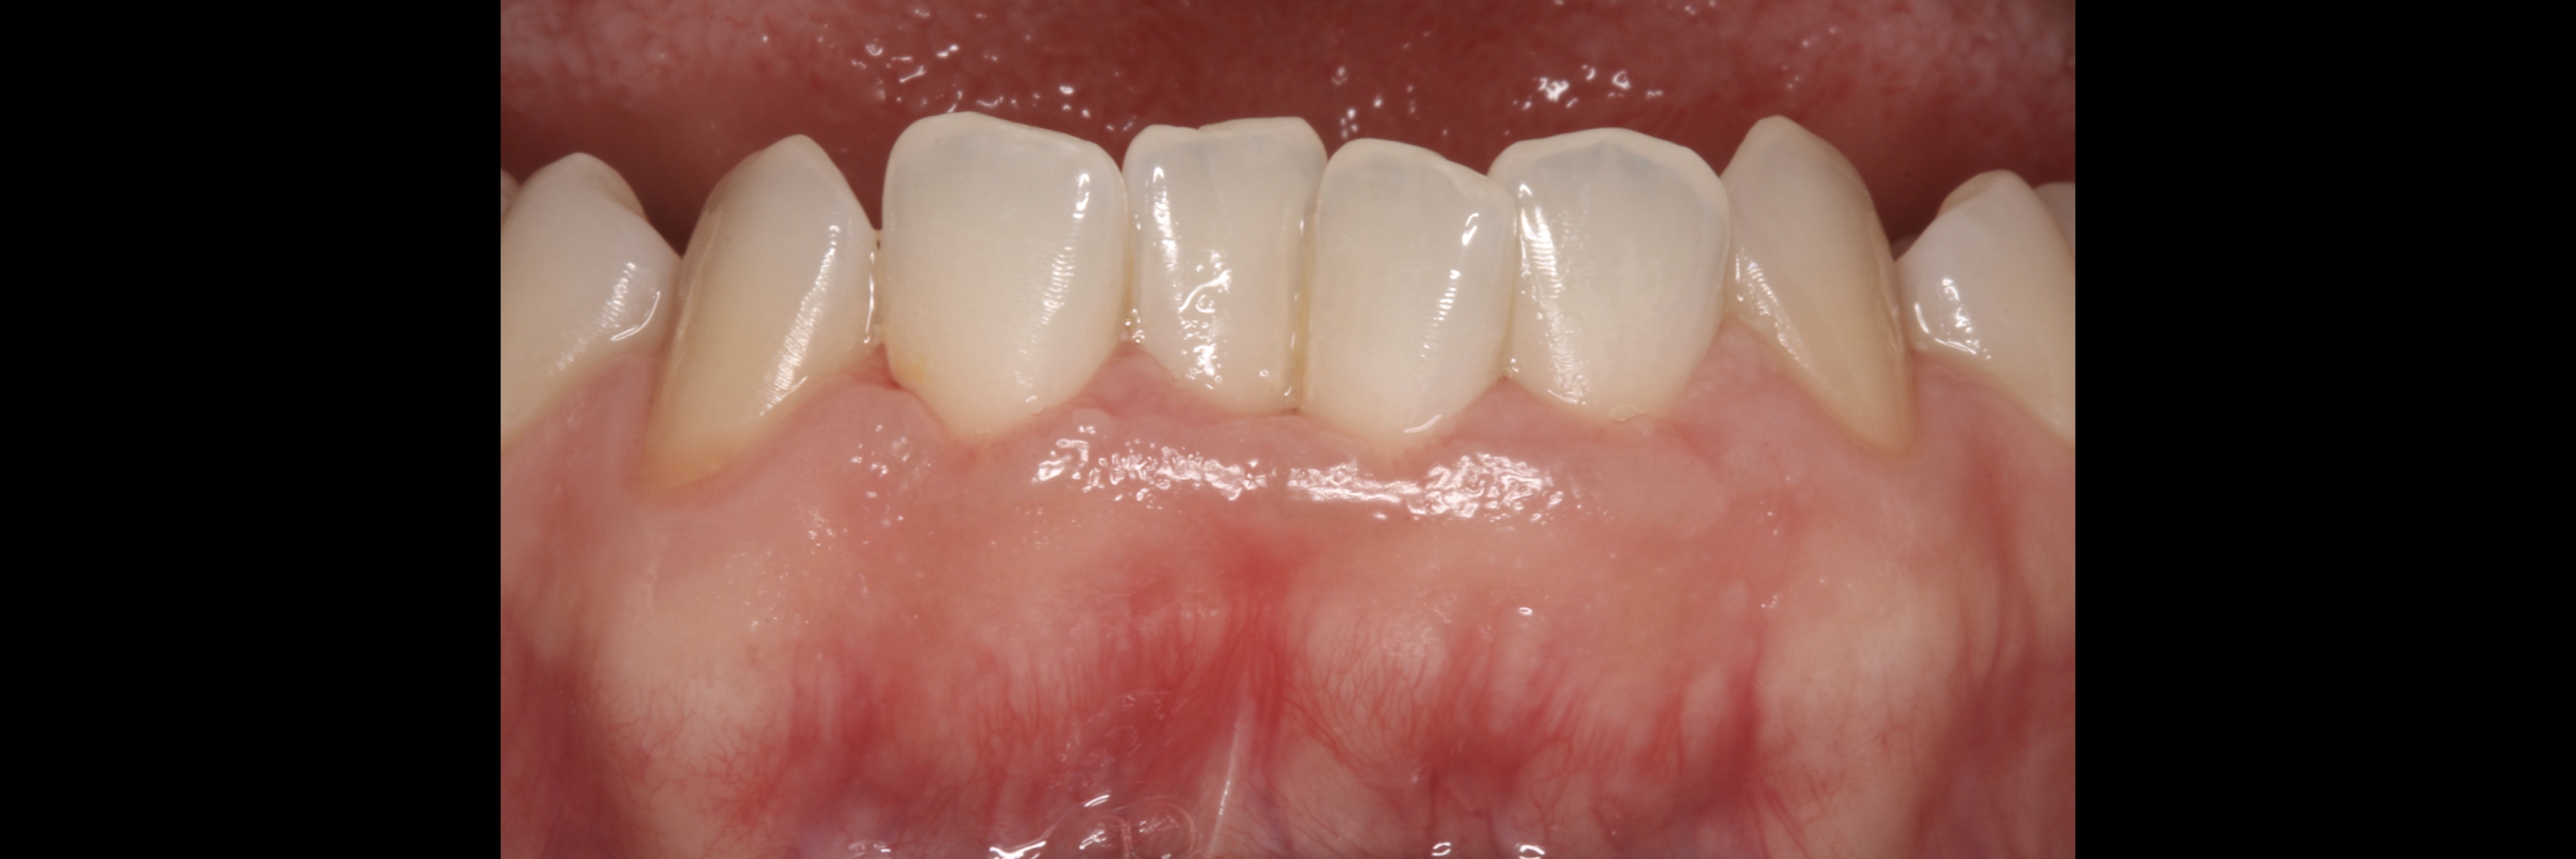

Alveolar Mucosa

Not Keratinized Gingiva              _________________

Keratinized Gingiva

The width of the keratinized gingiva may vary between 1 and 9mm.

Bowers, G.: A study of the width of attached gin­ giva. J. Periodont. 54:201-209, 1963.

Ainamo, J. and Löe, H : Anatomical characteristics of gingiva. A clinical and microscopic study of the free and attached gingiva. J. Periodont. 57:5-13, 1966.

However, the question of how much gingiva is "adequate" has still not been investigated.

There was no answer at the time of Lang and Löe's paper -1972 - and still nowadays we still lack a final answer, but attached gingiva plays a major role on stable soft tissues around teeth and implants.